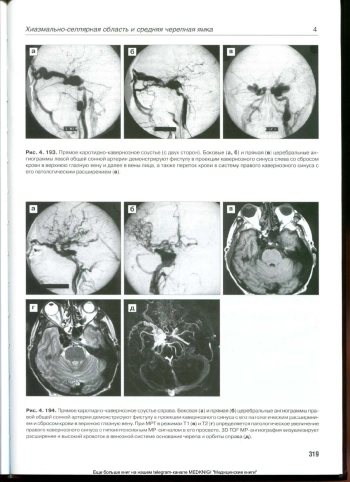

Представлено большое количество иллюстраций комплексной диагностики клинических наблюдений, некоторые из которых имеют уникальный характер и нами отдельно вынесены в галерию редких слу